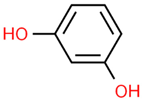

| Sr. No. | Name | PubChem ID | MF | MW | Canonical SMILES | Structure |

|---|---|---|---|---|---|---|

| 1 | Apigenin | 5280443 | C15H10O5 | 270.24 | C1=CC(=CC=C1C2=CC(=O)C3=C(C=C(C=C3O2)O)O)O |  |

| 2 | Caffeic acid | 689043 | C9H8O4 | 180.16 | C1=CC(=C(C=C1C=CC(=O)O)O)O |  |

| 3 | Catechin | 9064 | C15H14O6 | 290.27 | C1C(C(OC2=CC(=CC(=C21)O)O)C3=CC(=C(C=C3)O)O)O |  |

| 4 | Chlorogenic acid | 1794427 | C16H18O9 | 354.31 | C1C(C(C(CC1(C(=O)O)O)OC(=O)C=CC2=CC(=C(C=C2)O)O)O)O |  |

| 5 | Digalacturonic acid | 439694 | C12H18O13 | 370.26 | C1(C(C(OC(C1O)OC2C(C(C(OC2C(=O)O)O)O)O)C(=O)O)O)O |  |

| 6 | Ferullic acid | 445858 | C10H10O4 | 194.18 | COC1=C(C=CC(=C1)C=CC(=O)O)O |  |

| 7 | Gallic acid | 370 | C7H6O5 | 170.12 | C1=C(C=C(C(=C1O)O)O)C(=O)O |  |

| 8 | Iso-quercetin | 10813969 | C21H20O12 | 464.4 | C1=CC(=C(C=C1C2=C(C(=O)C3=C(C=C(C=C3O2)O)O)OC4C(C(C(C(O4)CO)O)O)O)O)O |  |

| 9 | Luteolin | 5280445 | C15H10O6 | 286.24 | C1=CC(=C(C=C1C2=CC(=O)C3=C(C=C(C=C3O2)O)O)O)O |  |

| 10 | Myricetin | 5281672 | C15H10O8 | 318.23 | C1=C(C=C(C(=C1O)O)O)C2=C(C(=O)C3=C(C=C(C=C3O2)O)O)O |  |

| 11 | p-coumaric acid | 637542 | C9H8O3 | 164.16 | C1=CC(=CC=C1C=CC(=O)O)O |  |

| 12 | Protocatechuic acid | 72 | C7H6O4 | 154.12 | C1=CC(=C(C=C1C(=O)O)O)O |  |

| 13 | Quercetin | 5280343 | C15H10O7 | 302.23 | C1=CC(=C(C=C1C2=C(C(=O)C3=C(C=C(C=C3O2)O)O)O)O)O |  |

| 14 | Resorcinol | 5054 | C6H6O2 | 110.11 | C1=CC(=CC(=C1)O)O |  |

| 15 | Rutin | 5280805 | C27H30O16 | 610.5 | CC1C(C(C(C(O1)OCC2C(C(C(C(O2)OC3=C(OC4=CC(=CC(=C4C3=O)O)O)C5=CC(=C(C=C5)O)O)O)O)O)O)O)O |  |

| 16 | β-Carotene | 5280489 | C40H56 | 536.9 | CC1=C(C(CCC1)(C)C)C=CC(=CC=CC(=CC=CC=C(C)C=CC=C(C)C=CC2=C(CCCC2(C)C)C)C)C |  |

| 17 |  | 222284 | C29H50O | 414.7 | CCC(CCC(C)C1CCC2C1(CCC3C2CC=C4C3(CCC(C4)O)C)C)C(C)C |  |